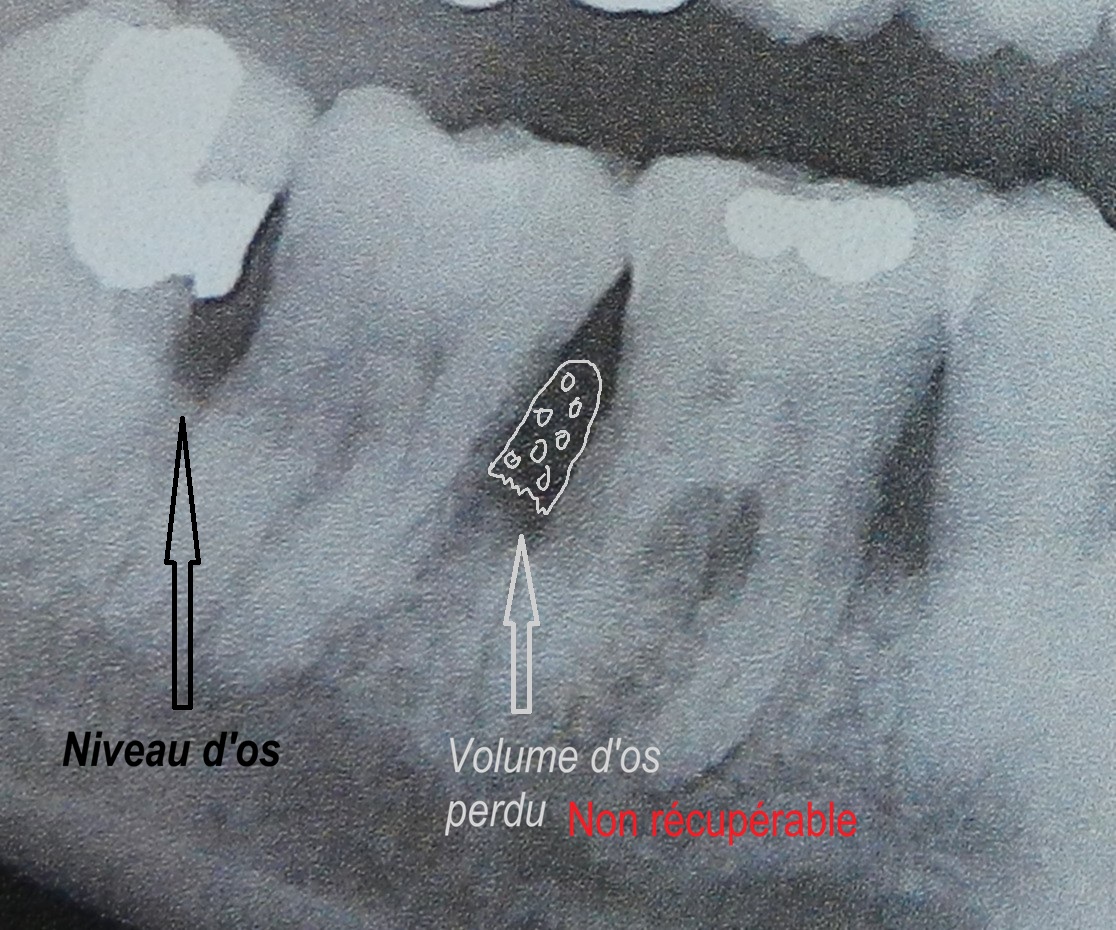

Voici pourquoi : 20 milliards de bactéries vivent dans votre bouche. Chaque jour, elles détruisent les tissus de soutien de vos dents. Et tout ce qui est perdu… est perdu pour toujours.

Une fois perdues, elles ne reviennent jamais